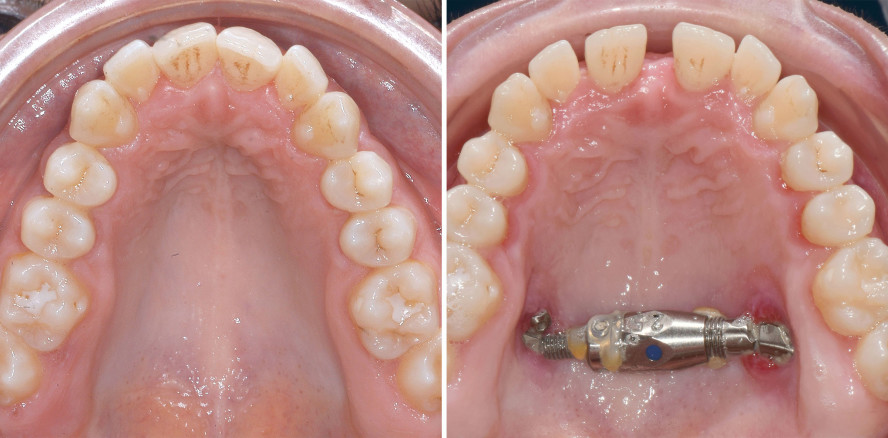

Die DC-VILA Gruppe bestand aus konsekutiv entbracketierten Patienten, die im Zeitraum von 2019 bis 2021 in einer kieferorthopädischen Fachpraxis (Bad Essen, Deutschland) behandelt wurden. Die transversale Dimension wurde an digitalen Modellen vor der Behandlung (T0; Abb. 4a–c) und nach dem Debonding (T1; Abb. 4d–f) gemessen. Alle Patienten dieser Gruppe wurden mit individuellen Bögen behandelt,38 die von einem Biegeroboter hergestellt wurden. Um die erforderliche transversale Korrektur zu erreichen, wurde ein 0,016"x 0,024" SS-Bogen mit Expansion von 1, 2 oder 3 cm im Oberkiefer und Kompression von 1 oder 2 cm im Unterkiefer eingesetzt (Abb. 5). Die entsprechenden Biegungen wurden im Interbracketabstand von 3-3 hinzugefügt.

Die vorliegenden Ergebnisse bestätigen die These, dass transversale Diskrepanzen von fünf Millimetern rein dentoalveolär korrigiert werden können.26,27 Bei Betrachtung der maximal erreichbaren Gesamtkorrektur des Kreuzbisses fällt auf, dass in beiden Gruppen die Werte an P2 (9,1 vs. 9,3 mm), M1 (10,1 vs. 11, 2 mm) und M2 (9,7 vs. 9,4 mm) vergleichbar waren (Tab. 2). Dies scheint überraschend, ist jedoch der Tatsache geschuldet, dass der Kreuzbiss in der nichtchirurgischen Gruppe in beiden Kiefern korrigiert wurde und nicht nur im Oberkiefer, wie in der SARPE Gruppe. Ein klinisches Beispiel einer transversalen dentoalveolären Kompensation ist in Abbildung 4 zusammengefasst.